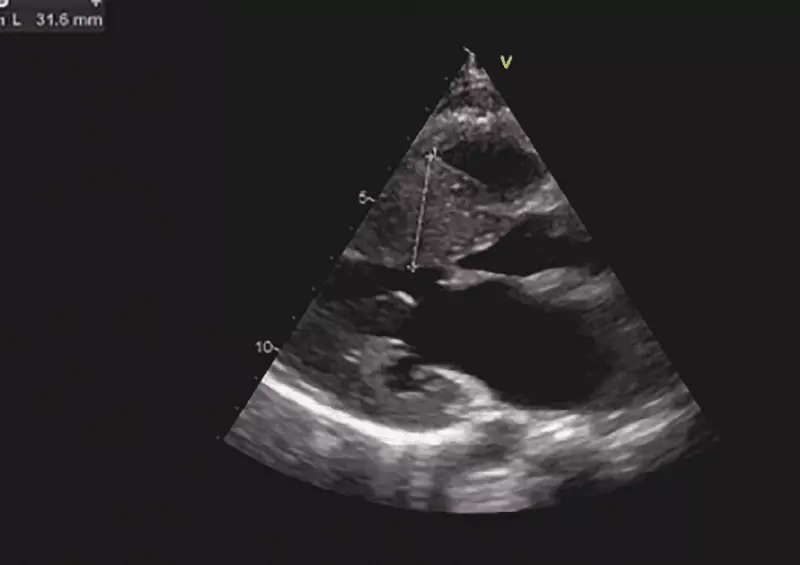

Odrębną, a jednocześnie najrzadszą grupę pacjentów z omdleniami kardiogennymi, stanowią pacjenci z chorobami organicznymi serca, które są przyczyną zaburzeń hemodynamicznych prowadzących do zmniejszenia przepływu mózgowego lub są substratem do istotnych zaburzeń rytmu serca. Zaliczamy do nich wady zastawkowe, np. zwężenie zastawki aortalnej, wypadanie zastawki mitralnej, dysfunkcje protez zastawkowych, złożone wady serca zarówno przed leczeniem operacyjnym, np. tetralogia Fallota, jak i po korekcji operacyjnej, wrodzone anomalie tętnic wieńcowych, kardiomiopatię rozstrzeniową, przerostową zawężającą i niezawężającą, arytmogenną dysplazję prawej komory, zapalenie mięśnia sercowego (ryc. 6).

W tej grupie pacjentów podstawowym badaniem diagnostycznym jest echokardiografia [18]. Tylko ocena anatomiczna, ocena przepływów w jamach serca i dużych naczyniach z użyciem funkcji Dopplera oraz pomiary jam serca pozwalają na postawienie rozpoznania nieprawidłowości strukturalnych i funkcjonalnych mięśnia sercowego. W szczególnych sytuacjach, gdy wykonane badania są niewystarczające na postawienie ostatecznego rozpoznania, sięgamy po dodatkowe metody badawcze. I tak w podejrzeniu ostrego rozwarstwienia aorty czy zatoru tętnicy płucnej metodą z wyboru pozostaje tomografia komputerowa z użyciem kontrastu. W przypadku podejrzenia masy patologicznej w obrębie jam serca, miokardium czy osierdzia, najlepszym wyborem pozostaje rezonans magnetyczny serca. W przypadku echokardiograficznego podejrzenia nadciśnienia płucnego jedynym weryfikującym badaniem pozostaje cewnikowanie serca.

Ryc. 6. Badanie echokardiograficzne dziewczynki 13-letniej z zasłabnięciami w czasie wysiłku w wywiadzie. Projekcja naczyniowa długa (a) i naczyniowa krótka (b) – widoczny istotny przerost przegrody międzykomorowej do około 31 mm (norma według BSA –10 mm). Na podstawie badania echokardiograficznego rozpoznano kardiomiopatię przerostową